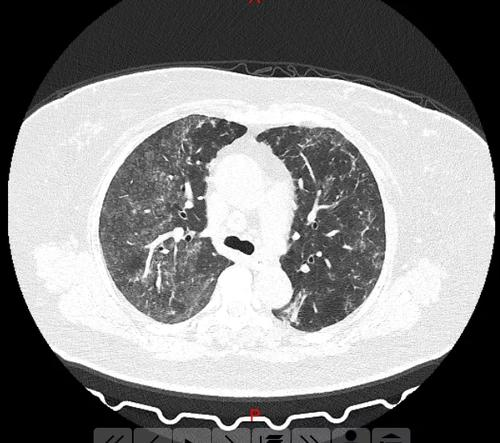

根据对已有的图片分析,得到图片的各个部分如下图2所示:

为了将肺部区域分割出来,要进行如下的操作:

(1)首先采用阈值分割法分割出粗略的肺部分,使用前面编写的myotsu函数来获取图像阈值,对图像进行二值化处理。

(2)分析得到的图片中胸腔部分为白色,而我们需要的是肺部分为白色,其他背景为黑色,所以对图像进行反色处理。

(3)然后通过系统函数bwlabel()标记连通区域,再统计各个连通区域的面积来对气管部分和背景置黑色来统一背景。

标记的原则如下:二值图像中值为 0 的区域 ( 对应于反色后图像中的胸腔内非肺区域 ) 作为背景,不予标记; 值≥1的区域 ( 对应于反色后图像中的目标肺组织区域、胸腔外区域和气管部分 ) 进行联通标记 , 并从数值 1 开始计数, 即标记 1 为第一个联通区域,标记2为第二个联通区域,以此类推。

由于反色后标记区域的面积不同,所以计算各个连通区域的面积,根据连通区域的标号规则得到背景和气管部分所在的标号。

再将根据面积大小找到的部分的像素点(即非肺区域)对应的原二值图像处赋值成 0,标记值大于 1 的像素点(即目标肺区域)对应的原二值图像处赋值成 1。